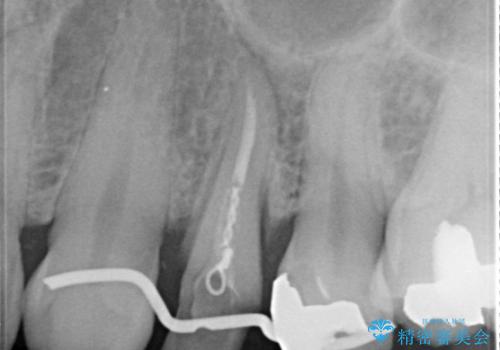

- 歯肉の下まで深く歯が折れたことを主訴に来院された患者様です。

かかりつけ医にて応急的に修復してますが根本的な治療を希望され、矯正的挺出を行ったのち、歯周外科を行い、歯冠修復をしております。

歯肉縁下の水平破折をきちんと治療するためには時間も費用もかかります。